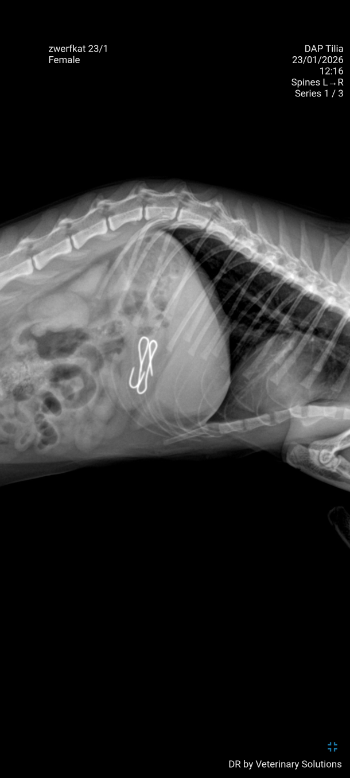

Bij nazicht door de dierenarts werd gevonden dat ze een ernstige breuk in haar bekken had opgelopen, waardoor de twee helften nu los van elkaar staan. Ook blijkt ze twee haakjes in haar maag te hebben 😔. Maar dit kleine vechtertje toonde zich van haar sterkste kant en probeert ondanks de pijn om rond te lopen en op de kattenbak te gaan, ook al gaat dat moeizaam 💪.